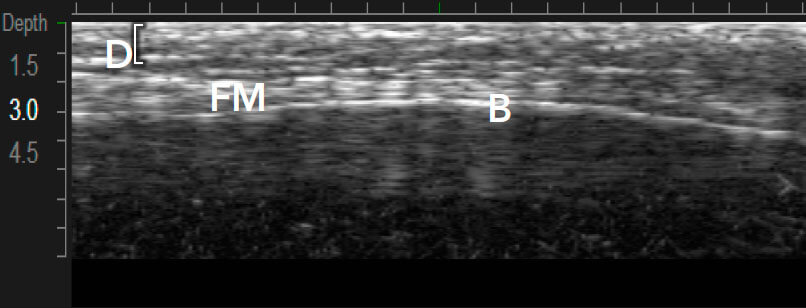

Ulthera – единственная технология с визуализацией в реальном времени

Примеры вариантов структуры кожи между индивидуальными пациентами1,12

Визуализация в реальном времени является основой Ultherapy®

Ultherapy® воздействует на ткани с помощью коллимированного звукового изображения. Затем доставляет микрофокусированный ультразвук с точной глубиной и температурой где лечение будет иметь наибольшее влияние.1,3

Визуализация в реальном времени необходима1,3,7:

Ultherapy® доставляет энергию на три глубины (1,5, 3,0 и 4,5 мм)1,7

MFU-V позволяет врачам точно видеть и учитывать все анатомические особенности в индивидуальном плане лечения, который будет являться эффективным.1